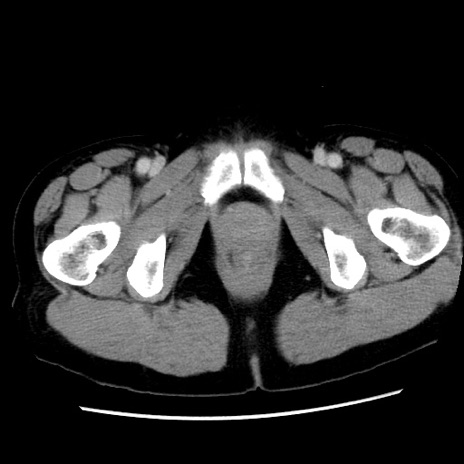

冠状断像